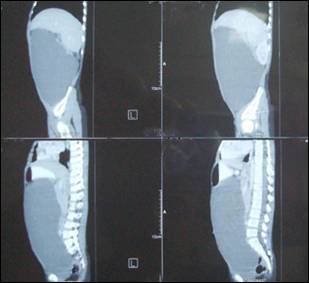

Image 1: CT scan, saggital section showing huge unilocular cystic

abdominal mass